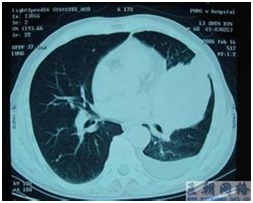

肺癌的治疗主要采用外科手术、放疗和化疗,外科手术仍是治疗早中期肺癌最有效的手段。但是对于中心型肺癌,由于病灶位置特殊,传统外科手术难以实施,患者往往失去了无进展生存的机会。中心型肺癌系指发生于支气管、叶支气管及肺段支气管的肺癌、以鳞癌和未分化癌居多。中心型肺癌一般很少使用手术治疗,这是因为中心型肺癌位于肺门附近,切除难度大,手术效果不理想,很容易诱发骨转移